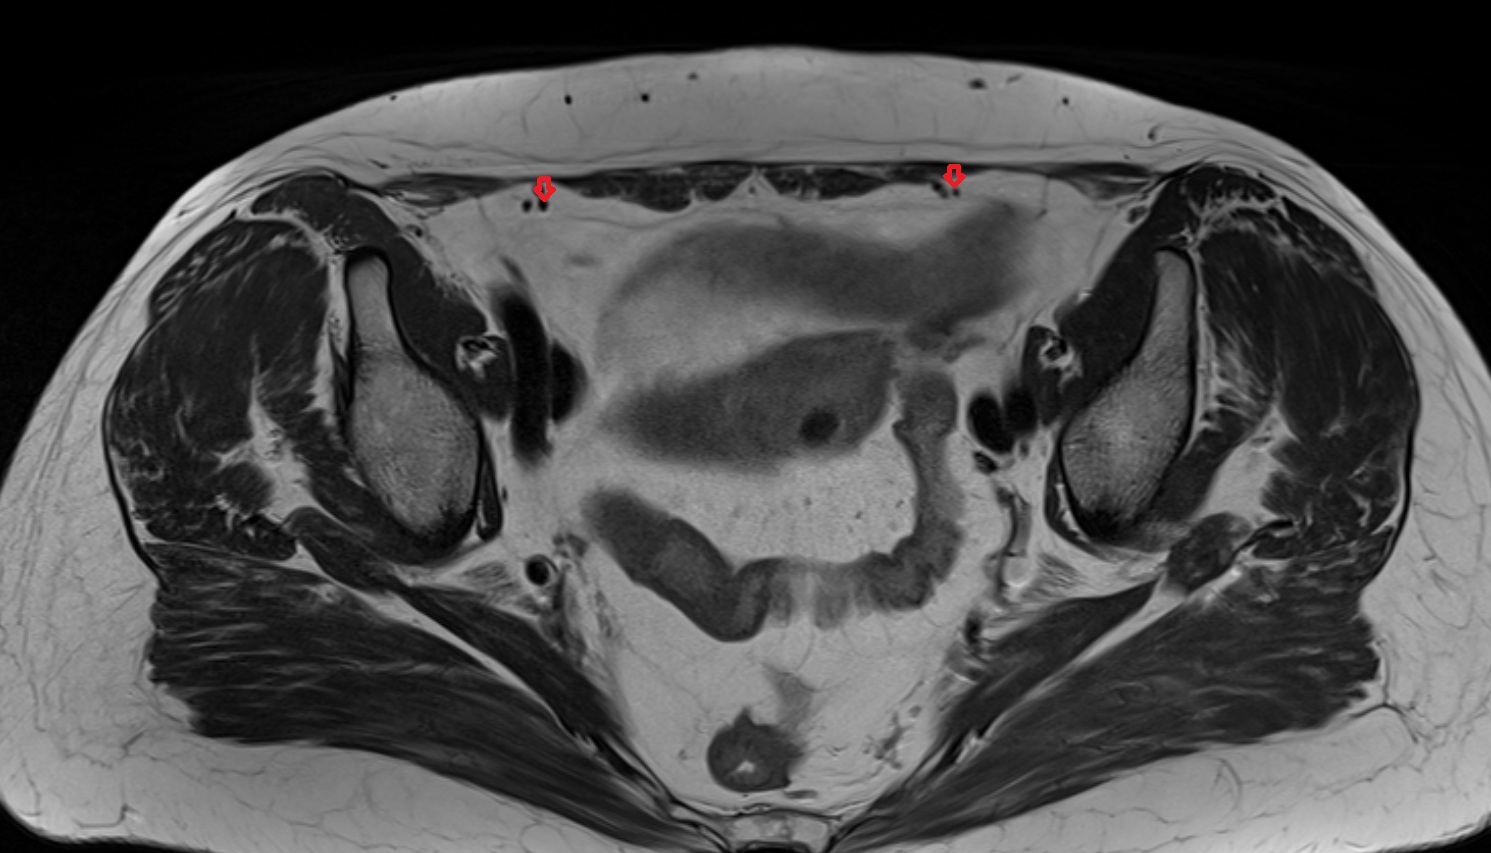

- Inguinal lymph nodes

- External iliac lymph nodes